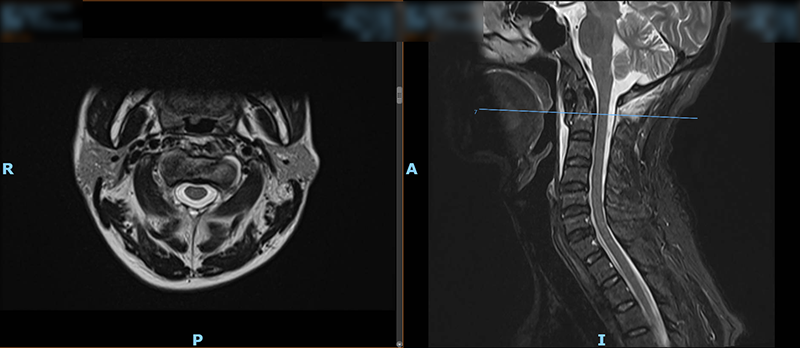

日前,47歲的王先生(化名)因外傷致頸部疼痛、活動(dòng)受限,在家人的陪同下,他來到柳州市人民醫(yī)院脊柱外科就診。結(jié)合MRI檢查結(jié)果,醫(yī)生診斷王先生為樞椎齒狀突II型骨折,需手術(shù)治療,王先生被收入脊柱外科病房。

▲術(shù)前MRI檢查結(jié)果

脊柱外科主任胡朝暉博士介紹,在頸椎損傷中,齒狀突骨折是累及寰樞椎區(qū)域穩(wěn)定性的嚴(yán)重?fù)p傷,發(fā)生率約占頸椎損傷的10%,由于具有特殊的解剖學(xué)結(jié)構(gòu),其不愈合發(fā)生率較高,不穩(wěn)定因素的存在,可導(dǎo)致急性及延遲性頸髓壓迫并危及生命。齒狀突骨折分為三型,其中Ⅱ型骨折是指涉及齒狀突頸部的骨折,此型骨折最為常見并且不穩(wěn)定,可見向前或向后移位。并且,寰樞椎部位解剖結(jié)構(gòu)復(fù)雜,手術(shù)區(qū)域靜脈竇血運(yùn)豐富,出血兇險(xiǎn),置釘時(shí)在狹窄區(qū)域需避開外側(cè)椎動(dòng)脈,內(nèi)側(cè)脊髓,真是“失之毫米,即是災(zāi)難”,一旦操作失誤或并發(fā)癥,病人就可能高位截癱,喪失呼吸功能生命難以維持。